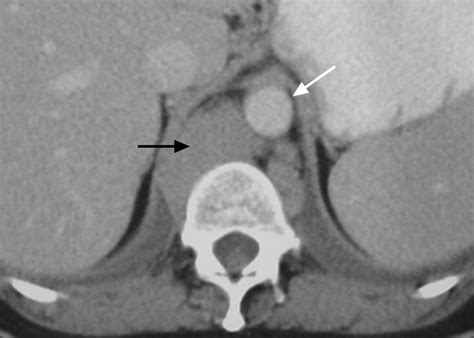

• Computed Tomography (CT) Scan: CT scans provide detailed images of the diaphragm and surrounding structures, aiding in the diagnosis of complex conditions.